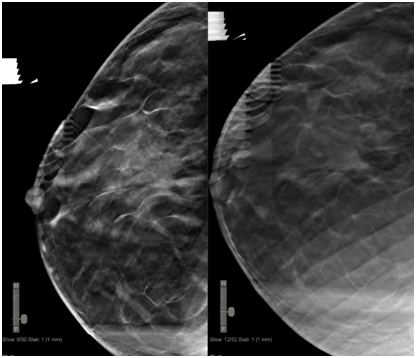

DBT-guided VAB allows use of the full detector size for imaging and provides lesion depth information without requiring triangulation. It facilitates target lesion re identification and sampling of even non-calcified masses.1,2 In our practice, the mean total procedure time was 15minutes. The mean time needed to identify and target the lesion was 2minutes (Figure 1 & 2).

Figure 1 First craniocaudal (CC) acquisition in which target is located at 6 mm away from the skin (left). Second CC acquisition with rolled view, where we located virtually the target deeper into the breast, which is 12 mm away from the skin (right). Lesion was an architectural distortion with anatomopathological result of a typical lobular hyperplasia.